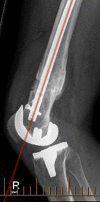

Multiple acceptable options are available for the correction of distal femoral deformity associated with knee arthritis. The treatment modality should be chosen based on the extent of deformity and attention to preservation of the collateral ligaments. Surgical options range from osteotomy alone, arthroplasty with intra-articular correction, or arthroplasty with extra-articular correction. Different implant choices and fixation methods for the osteotomy possess advantages and disadvantages which need to be considered carefully. In addition to discussing principles of management based on current literature, this article includes a case report using a previously undescribed technique using corrective osteotomy, intramedullary nail fixation, and total knee arthroplasty with computer navigation.